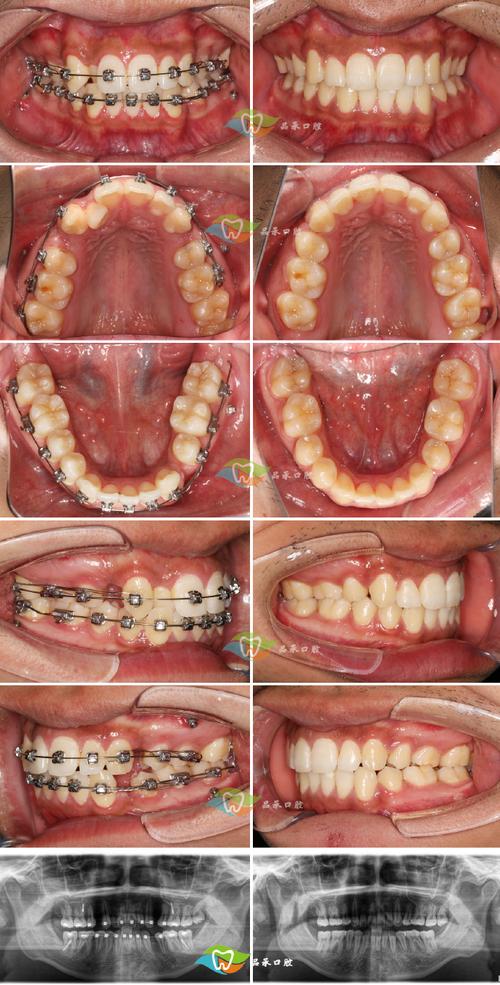

(图片来源网络,侵删) - 处理牙齿本身问题: